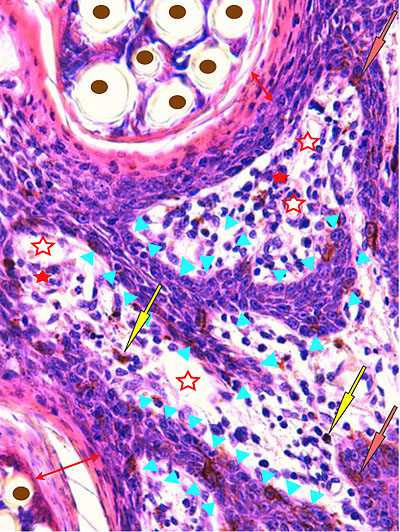

Photo 4 (Hémalun Eosine X 100) : aspect bleu de l’épiderme pour hyperplasie des couches basales, qui dessinent des crêtes épithéliales allongées, filiformes, ramifiées et branchues, peuplées de cellules basales hyperbasophiles. L’épiderme est multifocalement exulcéré. L’infundibulum folliculaire visible présente une hyperkératose parakératosique sans visualisation nette d’une couche des grains. Le derme montre une discrète angiectasie des capillaires du plexus superficial ainsi qu’un discret infiltrat inflammatoire périvasculaire superficial.

Légendes de la Photo 4 :

- Triangles bleus foncés : contours de crêtes épithéliales allongées, filiformes, ramifiées et branchues, peuplées de cellules basales hyperbasophiles.

- Triangles bleus clairs : exulcération épidermique

- Flèche rouge : parakératose épidermique et folliculaire

- Étoile rouge pleine :Le derme est faiblement à modérément inflammatoire (infiltrat mononucléé)

- Étoile rouge creuse : angiectasie des capillaires sanguins

- Étoile bleue claire : glandes sébacées

Photo 5 (Hémalun Eosine X 200) : ces crêtes épithéliales tout à fait particulières

(allongées, filiformes, branchues) peuvent également être présentes dans les couches les plus basales

de la gaine épithéliale folliculaire externe des infundibula folliculaires.

On note également l’aspect parakératosique diffus des infundibula folliculaires.

Légendes de la Photo 5 :

- Triangles bleus : contours de crêtes épithéliales allongées, filiformes, ramifiées et branchues, peuplées de cellules basales hyperbasophiles, émanant de la gaine épithéliale externe des infundibula folliculaires

- Flèches rouges : parakératose épidermique et folliculaire

- Étoiles rouge pleines : Le derme est faiblement à modérément inflammatoire (infiltrat mononucléé)

- Étoiles rouge claires : angiectasie des capillaires sanguins

- Ronds marrons : tiges pilaires